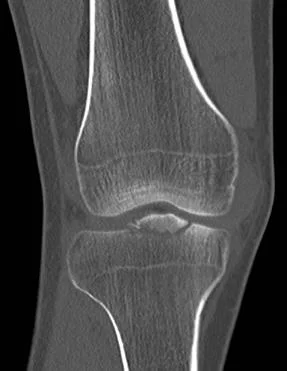

這張電腦斷層影像顯示脛骨近端中央有一個骨折碎片被拉起,這個位置正是前十字韌帶的附著點,因此最可能合併前十字韌帶的傷害。